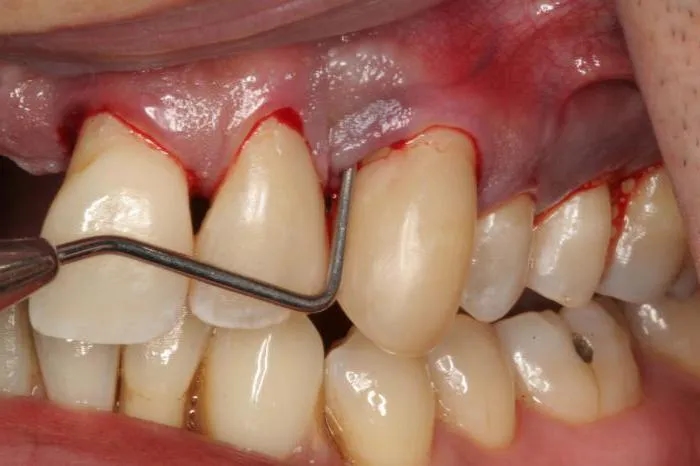

Jednym z pierwszych sygnałów recesji dziąseł są odsłonięte szyjki zębowe. To moment, gdy korzeń zęba staje się widoczny, co może prowadzić do dyskomfortu. Jeśli zauważysz, że Twoje zęby wydają się dłuższe, to może być znak, że dziąsła się cofają.

Nadwrażliwość zębów to kolejny częsty objaw. Może pojawić się ból podczas picia zimnych napojów lub jedzenia gorących potraw. Wrażliwość ta wynika z odsłonięcia korzeni, które nie są chronione przez szkliwo. Warto również zwrócić uwagę na krwawienie dziąseł, które może występować podczas szczotkowania.

Diagnostyka recesji dziąseł zaczyna się od dokładnego badania stomatologicznego. Dentysta ocenia stan dziąseł, mierzy głębokość kieszonek dziąsłowych i sprawdza, czy nie ma oznak stanu zapalnego. To pierwszy krok do postawienia właściwej diagnozy.